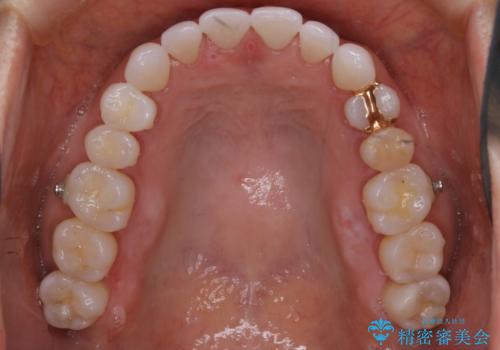

- 歯ぎしりや食いしばり、噛み合わせの治療とガタつきを治したいとのことでご来院されました。

検査の結果、前歯と臼歯の高さに差があり、前歯が全く当たらない状態になっているため歯ぎしりによって奥歯が削れてしまっているという状態でした。

マウスピースの矯正装置を用い、ガタつきを治しつつ奥歯を沈めていくことで噛み合わせ全体の改善を図りました。